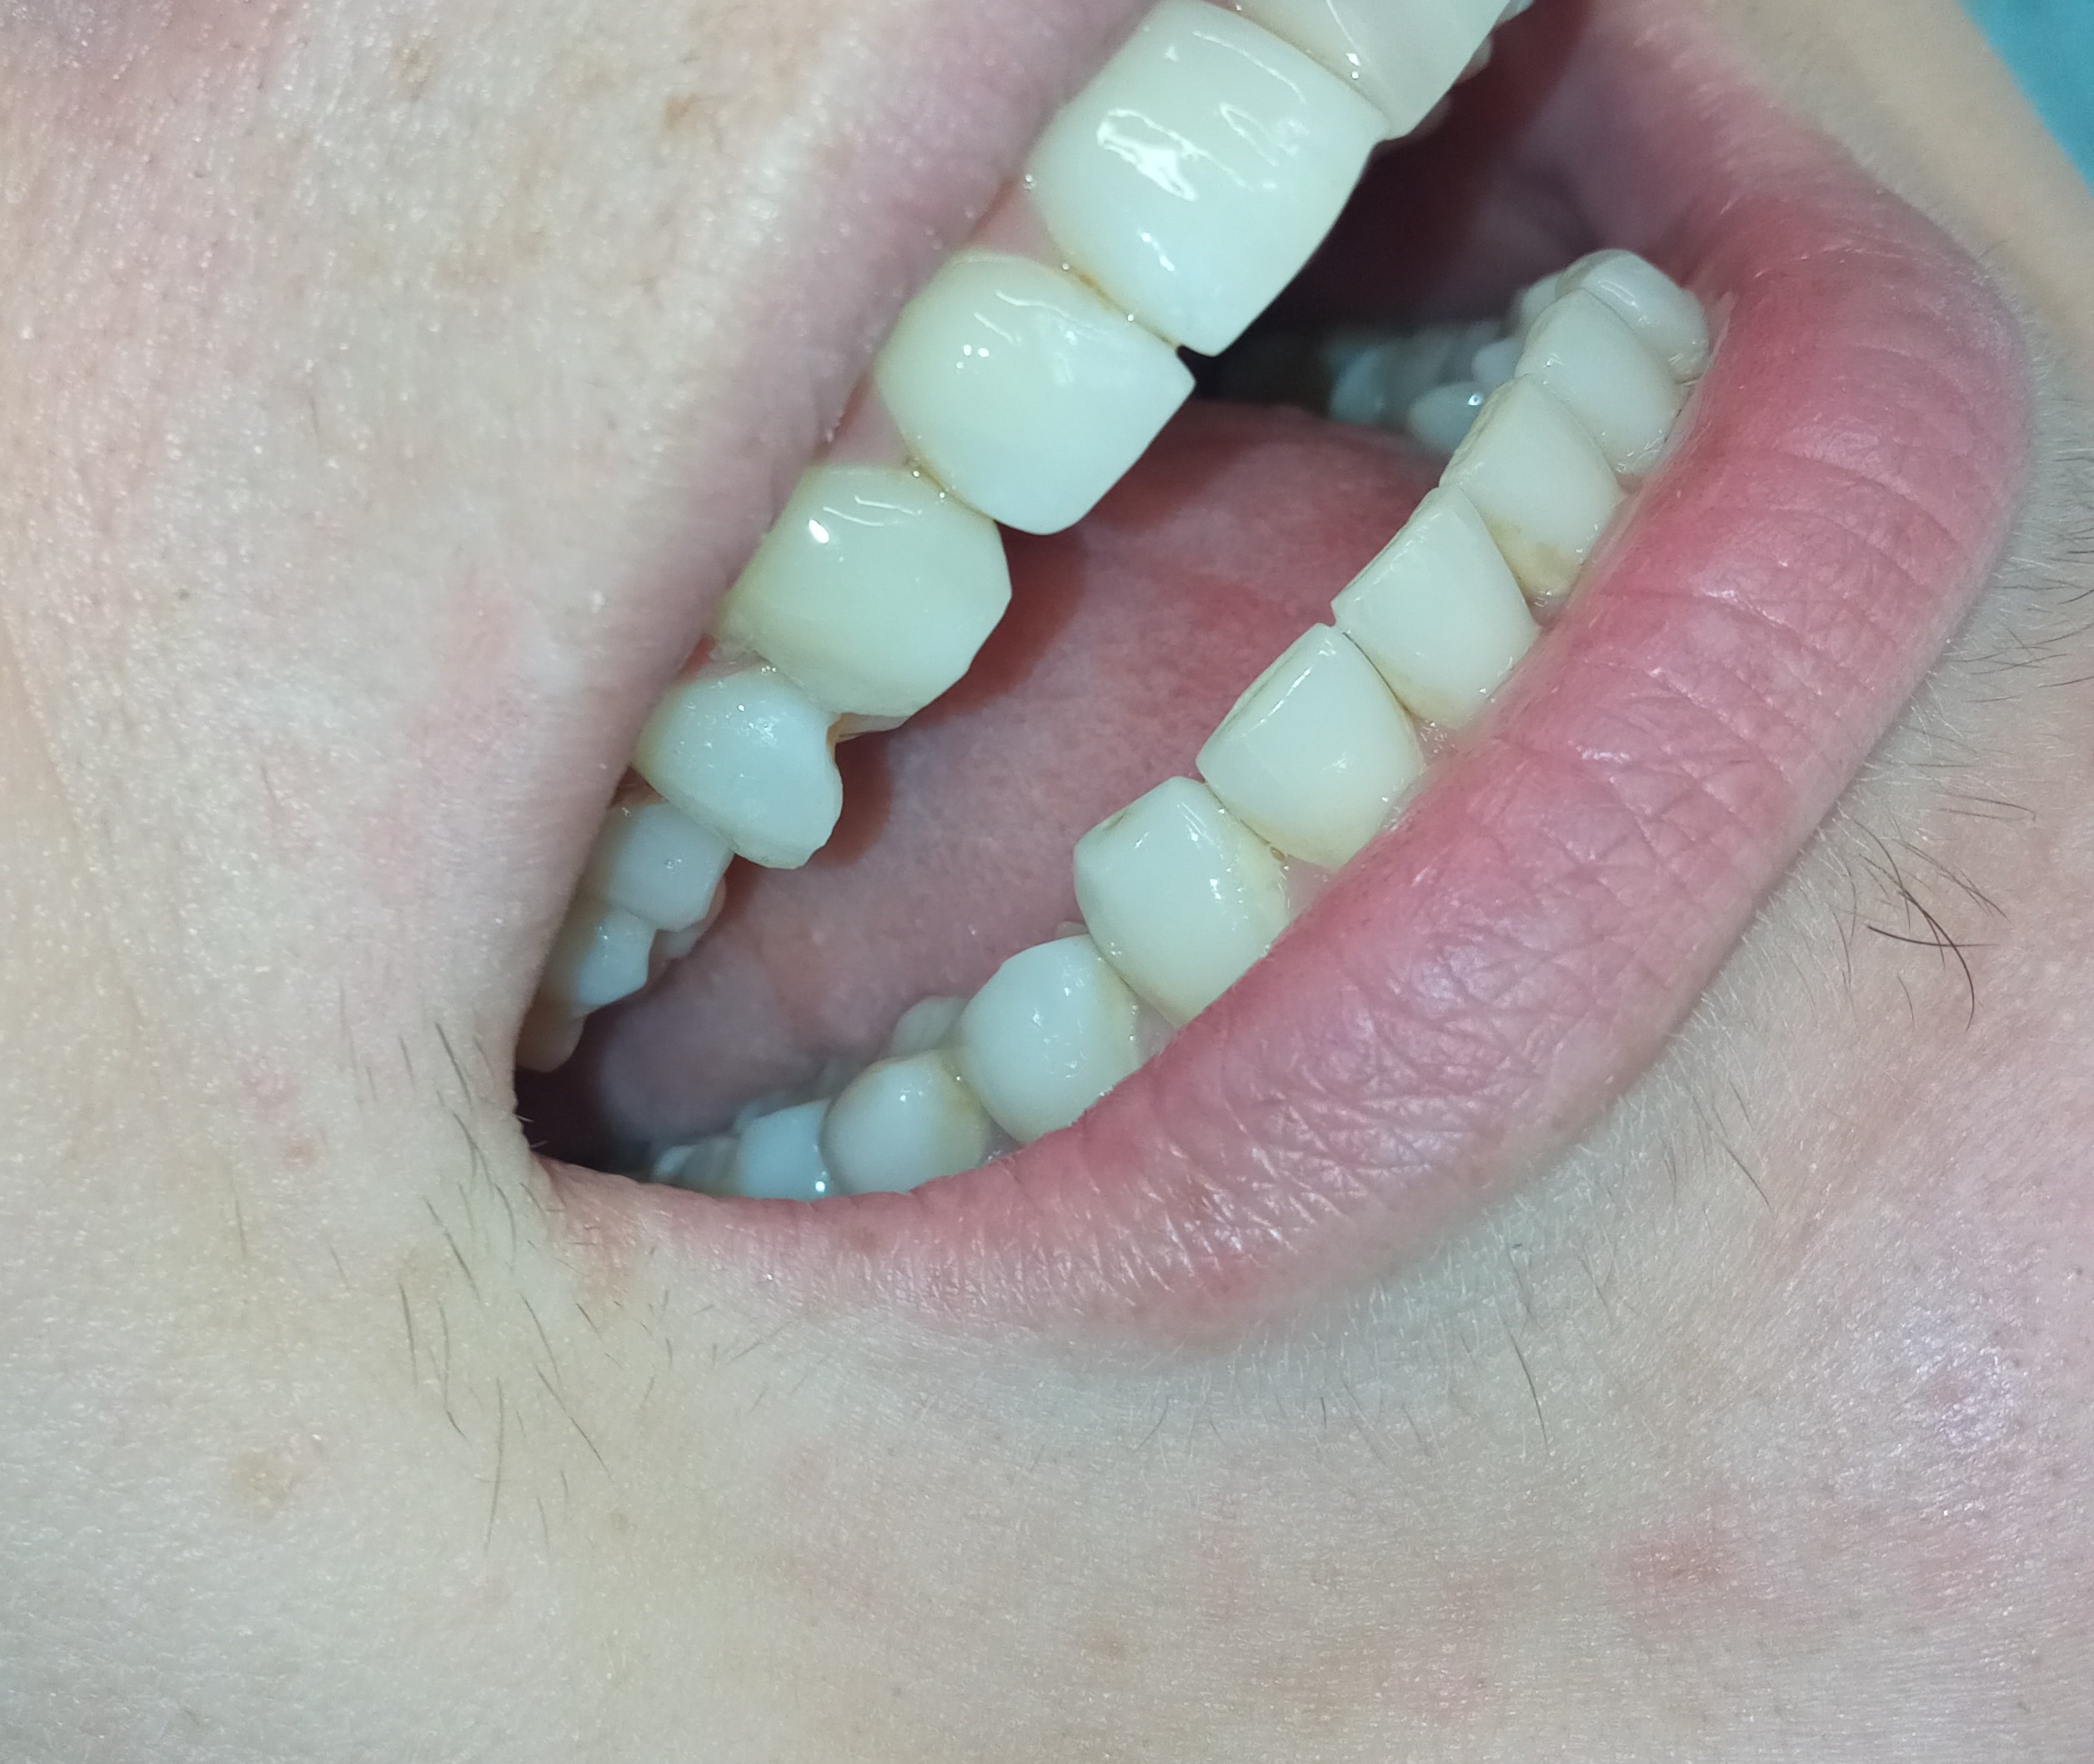

Αρχική κλινική εικόνα των 6 άνω πρόσθιων δοντιών

Προσωρινή αποκατάσταση των 6 άνω πρόσθιων δοντιών